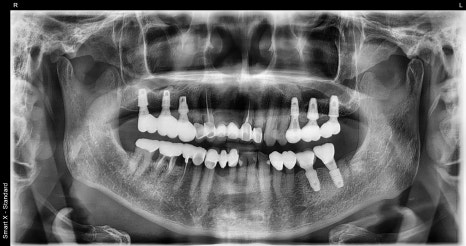

Left image: A panoramic X-ray taken after completion of the #25-27 prosthesis.

Right image: The prosthesis was finished with zirconia that is aesthetic and durable, like natural teeth.

🦷 Although this patient was elderly and had poor conditions, with the existing teeth significantly worn down and short crown height,

through the representative director’s precise surgery and planning, we were able to complete the treatment safely and satisfactorily.